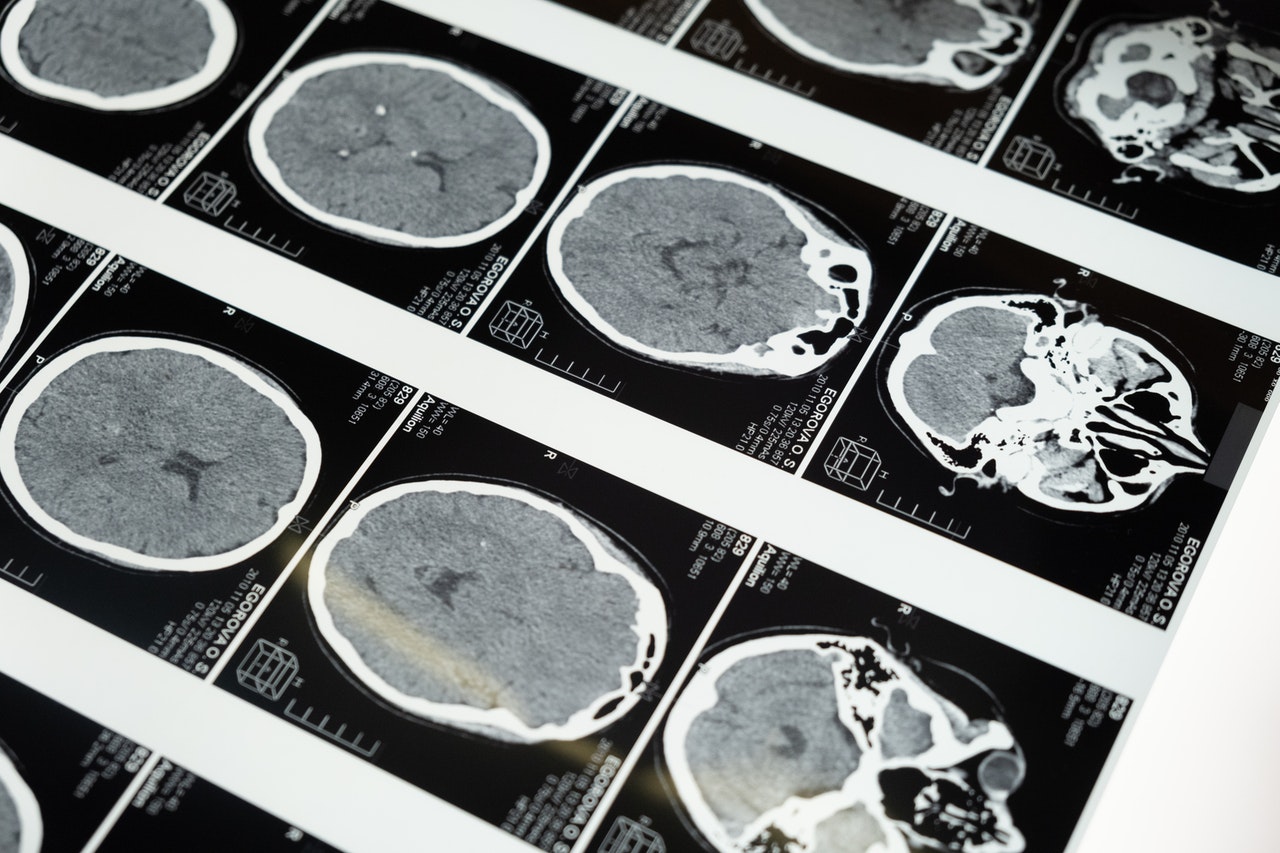

頭蓋内にてんかんを引き起こす原因が明らかにあるものです。

原因としては脳腫瘍、脳炎、血管障害、脳奇形などが挙げられます。